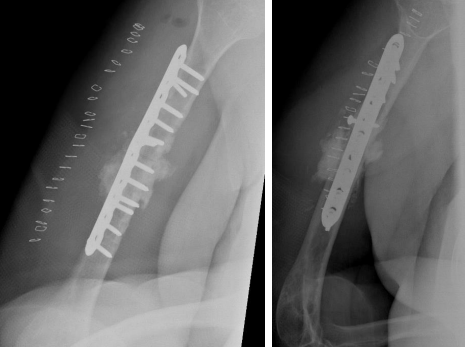

The patient was admitted and taken for her fourth surgery (third revision) on 1 August 2020. The implant and iliac crest bone graft were removed. Fibrous tissue was debrided, and fracture edges were freshened and medullary canals reopened. A 5 cm fibular autograft was harvested and placed in the bone defect, and fixation was performed with a broad 4.5 cm locking compression plate with cemented screws for proximal fixation. Postoperative radiographs are shown in Figure 6.

Figure 06

On serial follow-ups, the patient showed slow healing up to 6 months postoperatively. Follow ups continued for another 6 months but showed no progression of callus. Arrested partial healing was confirmed on CT scans, despite stable fixation, and the patient was symptomatic in the form of pain limiting daily activities. A bone scan was performed to evaluate for infection as the cause of partial healing and showed no evidence of infection. Radiographs at the 1-year follow-up are shown in Figure 7.

Figure 07

At that time, the primary surgeon decided to transfer the case to the Trauma unit, where the patient was reviewed thoroughly and all necessary investigations was made, after detailed discussion of the case and the options, we decided to go for another revision but with some tactical modifications. The patient was taken for yet another surgery, for the fifth time (fourth revision) on 30 November 2020. The same incision site was used, and the previous plate was removed and sclerotic bone debrided. An intramedullary cancellous bone graft was obtained from the patient’s left femur with the aid of a reamer-irrigator-aspirator. A titanium mesh cage was used to bridge the bone defect, and the graft from the left femur intramedullary canal was packed inside the titanium mesh cage. Primary fixation was obtained with a long proximal humerus locking plate laterally and augmented with a 3.5 cm locking compression plate anteriorly sat 90 degrees orientation.

Finally, 5.6 mL of rhBMP-2, on an absorbable collagen sponge carrier (ACS), was applied to the nonunion site. Postoperative radiographs are shown in Figure 8. Postoperatively, the patient suffered radial nerve neuropraxia, managed with splinting, and fully recovered 5 months postoperatively. Serial follow-ups for 21 months postoperatively showed complete healing clinically and radiographically, restoration of functional range of motion with the help of physiotherapy, and a painless functional limb. Radiographs are shown in Figure 9.

Figure 08

Figure 09